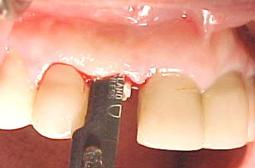

Figura n°1. Caso clínico: Paciente de 46 anos de idade, já portadora de 4 implantes, colocados há 6 anos, compareceu ao consultório após a perda da coroa do dente 12 com fratura da raiz.

Figura n°2. A análise radiográfica, mostrou uma raiz com muito pouca implantação, reação apical e ao exame clínico uma provável linha de fratura, transversal, alterando o ligamento periodontal no terço médio da raiz. Assim a raiz foi condenada, e indicado à paciente um implante imediato. Na radiografia pode-se observar outras alterações nos ápices dos dentes 13 e 14.

Figura n°3. Esta é a fotografia antes da cirurgia para implante. A imagem não ficou boa, mas pode-se notar com atenção uma linha de fratura iniciando na região vestibular com direção à distal.

Figura n°4. Esta fotografia mostra a incisão inicial, intra-sulcular, com lâmina N15, para melhor aproveitamento do tecido mole na reconstrução da gengiva marginal do implante. O retalho deve sempre ser total, ou seja, muco-perióstico.